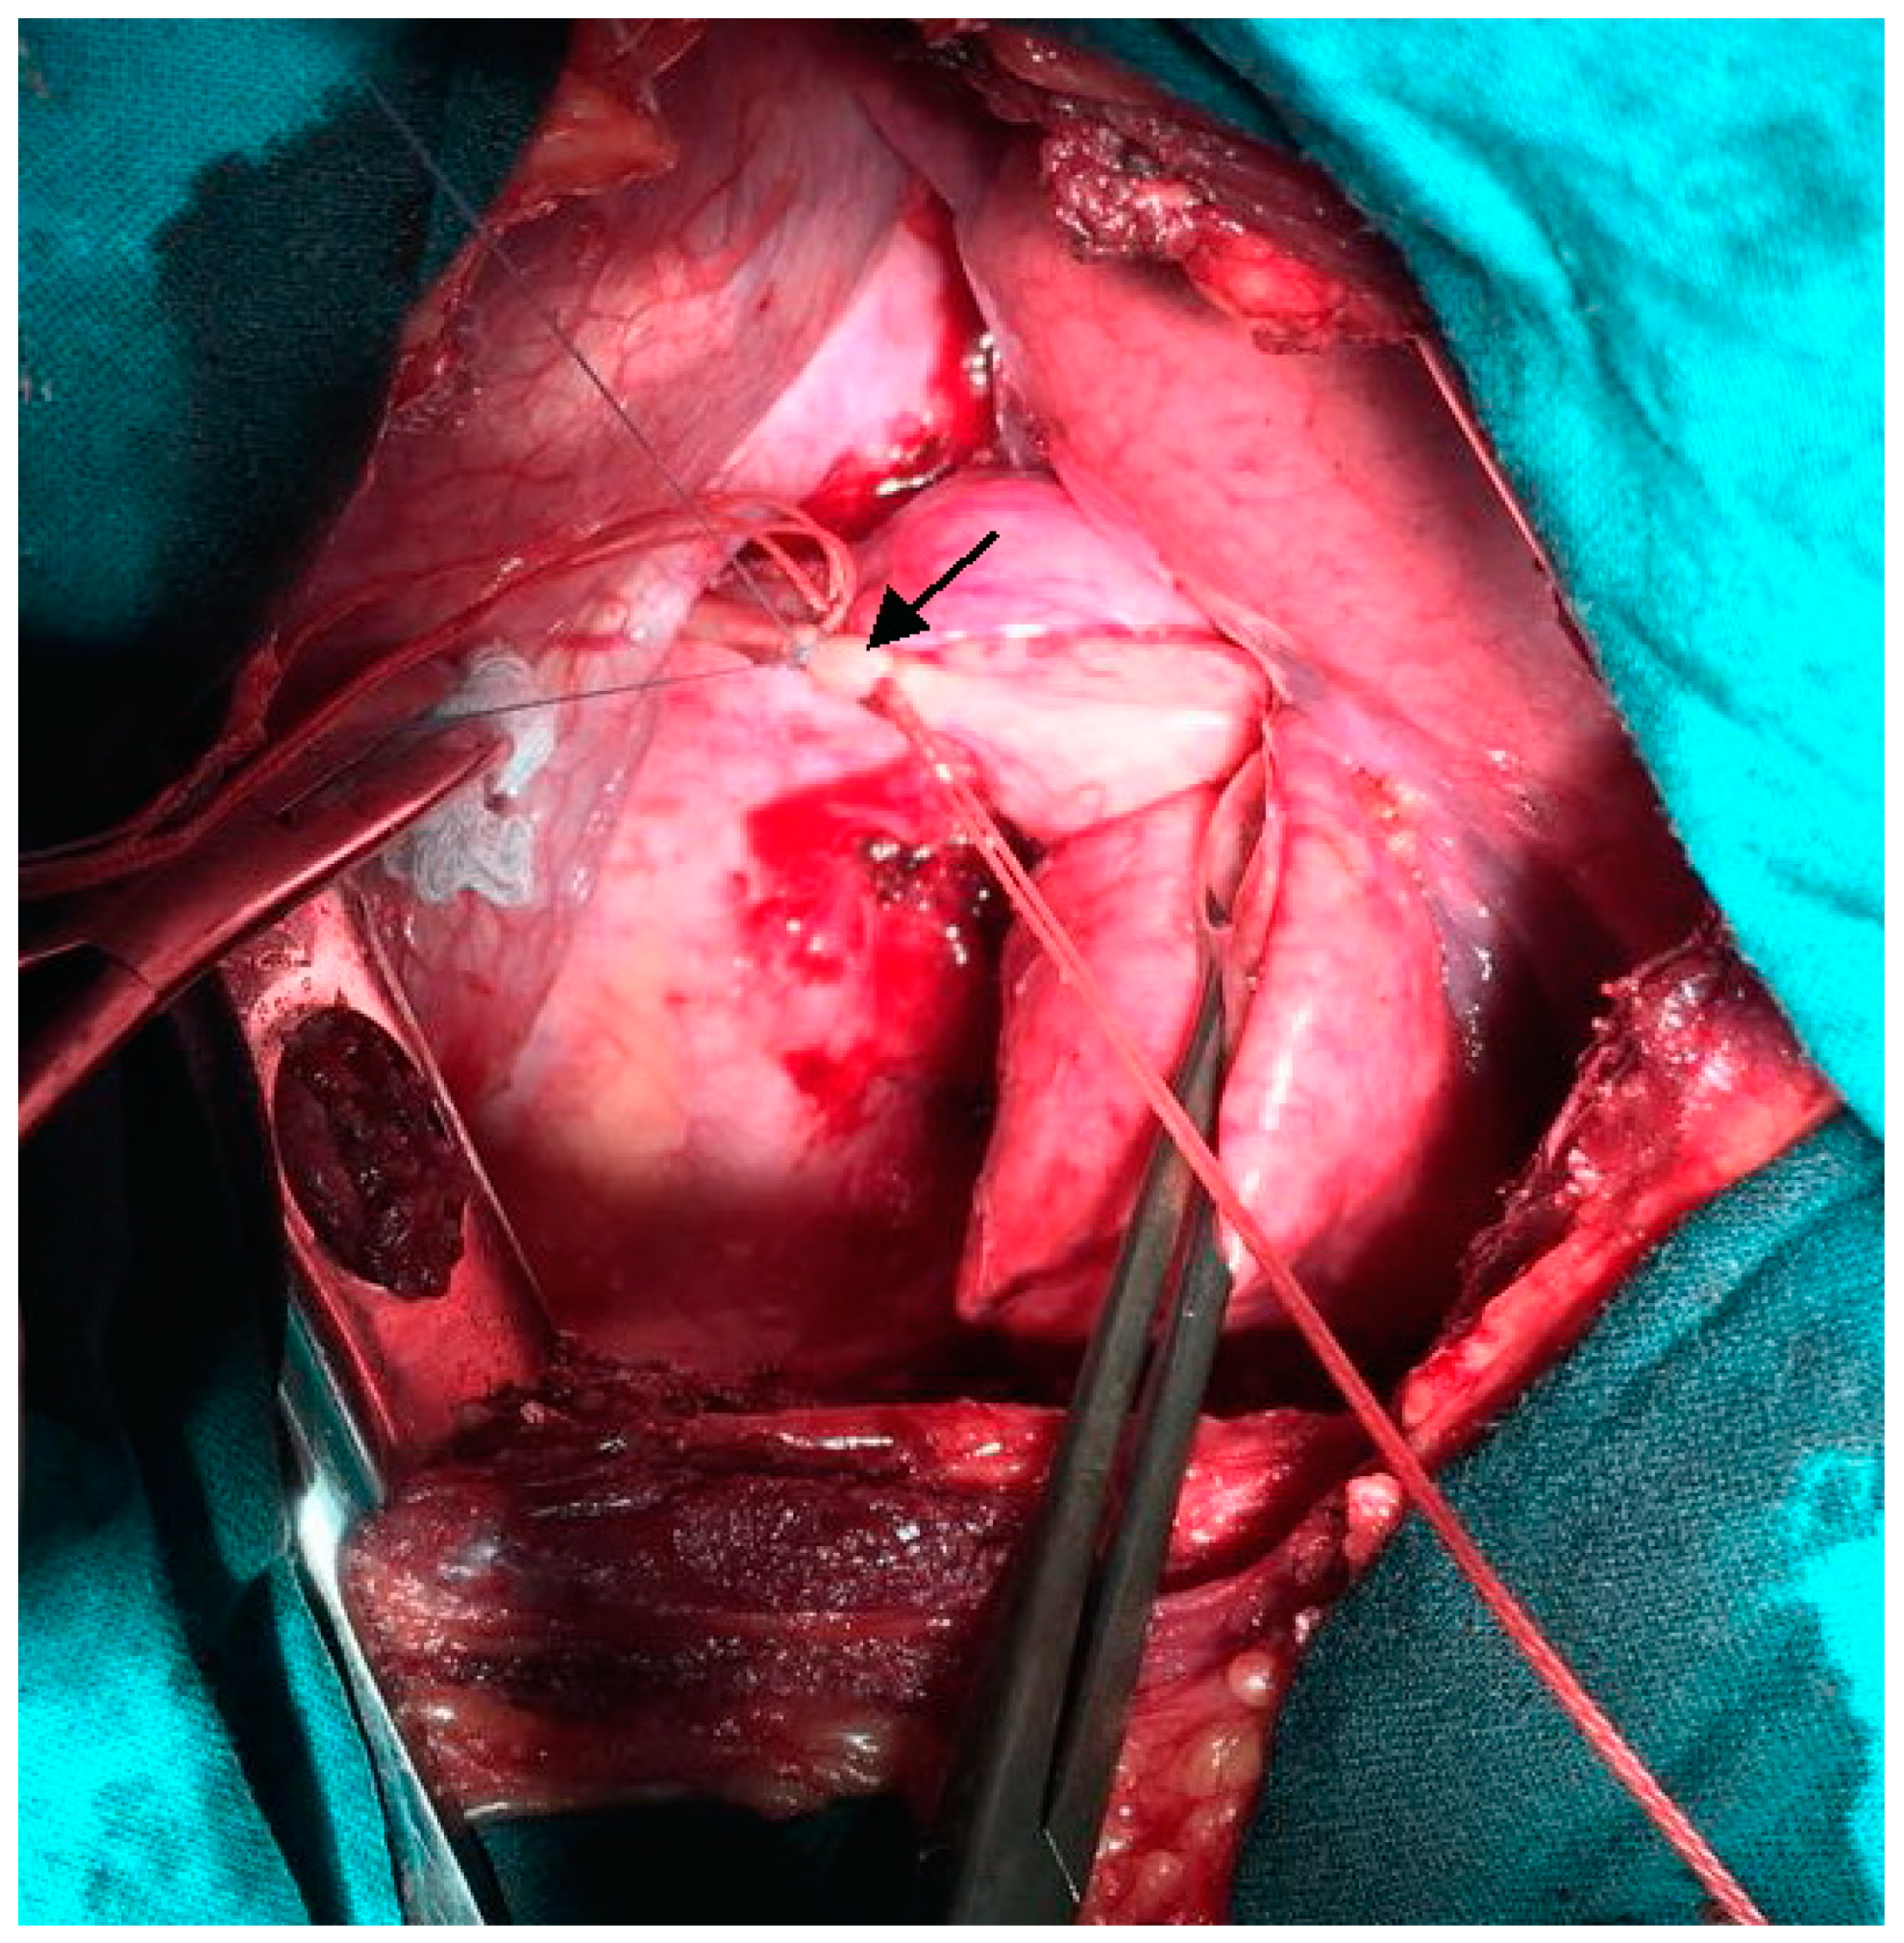

We performed left-sided posterolateral thoracotomy in the seventh intercostal space. The intrapulmonary sequester was characterized by an unventilated area of lung tissue at the posterior-basal segment (S10) of the inferior lobe. In accordance with CT findings, the pulmonary sequester was supplied by an arterial vessel with a diameter of 5 mm. The artery traversed the diaphragm. We ligated the artery carefully before transection (Figure 3).

Figure 3.

Intra-operative photograph: Ligation of the anomalous feeding artery (indicated by arrow) supplying the pulmonary sequester.

We carried out atypical resection of the sequester located in the inferior lobe of the left lung using a linear stapler. Histologic examination confirmed intralobar pulmonary sequestration with bronchiectases of different sizes, emphysema, and enlarged bronchi. Focal clusters of macrophages and lymphoid infiltrates were observed in the interalveolar septum and inside the lumen of alveoli.